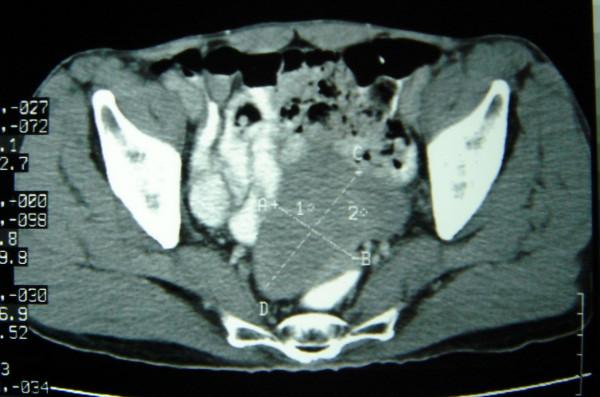

A 65 year old gentleman, presented with a pelvic mass. On exploratory laparotomy, it turned out to be gastrointestinal stromal tumour (GIST) arising from Meckel's diverticulum. Short history and review of literature are discussed.

Neoplasms occurring from Meckel's diverticulum, even though rare, should be considered as differential diagnosis of pelvic masses arising from bowel, wherever imaging modalities fail to give a definitive diagnosis.